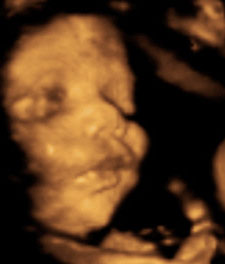

Ой! сами понимаете - счастью нет предела!!!! Такой он уже там хорошенький, пухленький и уже совсем похож на новорожденного малыша. Вот, полюбуйтесь! Фотки нам распечатали, но сканера дома нет. Так что вашему вниманию предлагаю фото в 3д, которую вырезала из видео. На распечатке кадр лучше и четче... но что ж поделать, его нам почему-то на сохранили на диск, только распечатали. Так что вот вырезка из видео:

Сынок наш пока мы с врачом вместе пытались его разбудить, стал тереть глазки, перекладывать под щечку другую руку. Одним словом, всячески давал нам понять, чтобы мы уже отстали от него и не мешали своими лучами :)) Ну что ж... недолго нам ждать осталось, потерпим еще чуток! И уже возьмем его на руки, обнимем крепко-крепко нашу кровиночку!!!!!